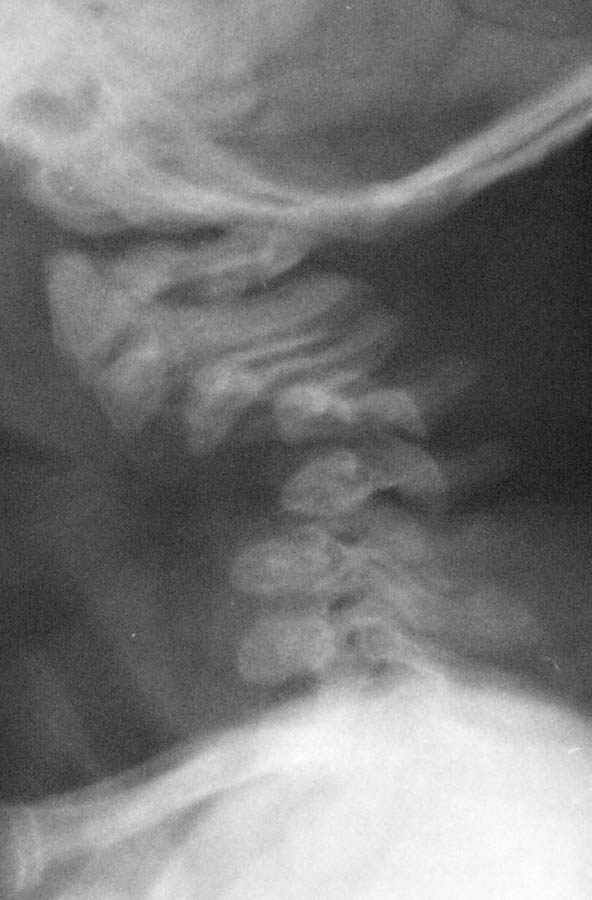

Девочка 5 месяцев, дочь коллеги, врача-анестезиолога, тетрапарез, в ногах спастический в руках - вялый, усугубившийся после "мануальной терапии".

Данные рентгена,КТ и МРТ прилагаются. Кроме того, имеется двухсторонний врожденный вывих бедра.По совокупности данных - болезнь Ларсена.В шейном отделе - дисплазия и гипоплазия суставных отростков С3-С5 с передним подвывихом и антелистезом, патологическим кифозом и стенозом позвоночного канала до 55% от исходного (5 мм при исходном 9 мм). Spina bifida occulta в 5 сегментах, в том числе расщепление задней дуги атланта, агенезия его передней дуги. Признаки спинальной компрессии и диффузной миелопатии на уровне стеноза.Вопрос - возможно ли в таком нежном возрасте оперативное лечение и вообще, какая должна быть тактика ?